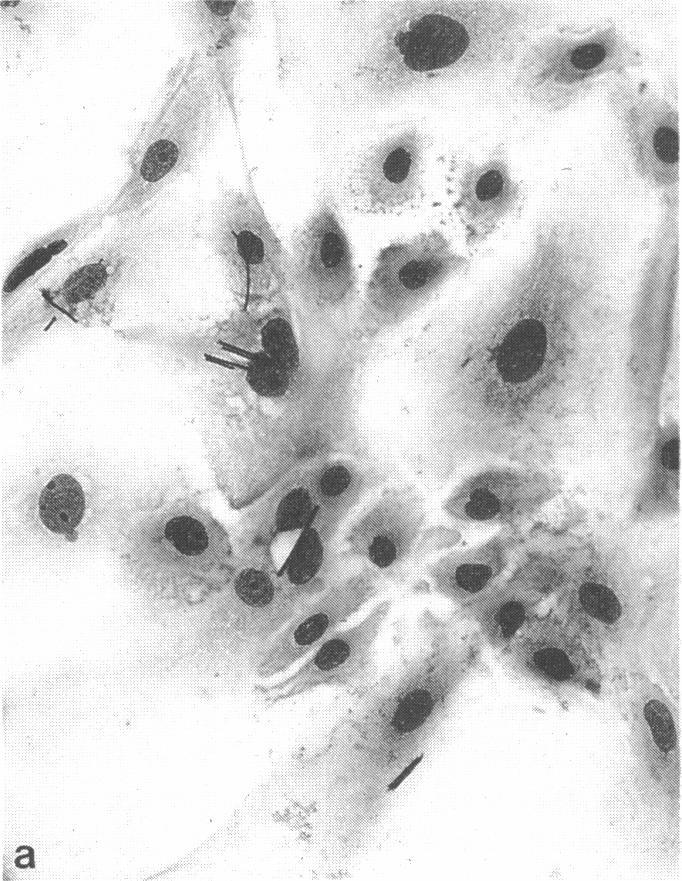

The dissolution rate of glass fibers has been shown to be pH sensitive using in vitro lung fluid simulant models. The current study investigated whether there is a difference in phagosomal pH (ppH) between rat alveolar macrophages (AM) and rat nasal epithelial cells (RNEC) and whether such a difference would influence the dissolution of glass fibers. The ppH was measured in cultured AM and RNEC using flow cytometric, fluorescence-emission rationing techniques with fluorescein-labeled, amorphous silica particles. Glass fiber dissolution was determined in AM and RNEC cultured for 3 weeks with fast dissolving glass fibers (GF-A) or slow dissolving ones (GF-B). The mean diameters of GF-A were 2.7 microns and of GF-B, 2.6 microns, the average length of both fibers was approximately 22 to 25 microns. Dissolution was monitored by measuring the length and diameter of intracellular fibers and estimating the volume, assuming a cylindrical morphology. The ppH of AM was 5.2 to 5.8, and the ppH of RNEC was 7.0 to 7.5. The GF-A dissolved more slowly in RNEC than in AM, and no dissolution was evident in either cell type with GF-B. The volume loss with GF-A after a 3-week culture with AM was 66% compared to 45% for cultured RNEC. These results are different from those obtained using in vitro lung fluid-simulant models where dissolution is faster at higher pH. This difference suggests that dissolution rates of glass fibers in AM should not be applied to the dissolution of fibers in epithelial cells.

使用体外肺液模拟模型已表明玻璃纤维的溶解速率对pH敏感。本研究调查了大鼠肺泡巨噬细胞(AM)和大鼠鼻上皮细胞(RNEC)之间吞噬体pH(ppH)是否存在差异,以及这种差异是否会影响玻璃纤维的溶解。使用流式细胞术、荧光发射定量技术和荧光素标记的无定形二氧化硅颗粒,在培养的AM和RNEC中测量ppH。用快速溶解的玻璃纤维(GF-A)或慢速溶解的玻璃纤维(GF-B)对AM和RNEC进行3周培养后,测定玻璃纤维的溶解情况。GF-A的平均直径为2.7微米,GF-B的平均直径为2.6微米,两种纤维的平均长度约为22至25微米。通过测量细胞内纤维的长度和直径并假设其为圆柱形形态来估计体积,从而监测溶解情况。AM的ppH为5.2至5.8,RNEC的ppH为7.0至7.5。GF-A在RNEC中的溶解速度比在AM中慢,并且在两种细胞类型中,GF-B均未观察到明显溶解。与培养的RNEC的45%相比,AM培养3周后GF-A的体积损失为66%。这些结果与使用体外肺液模拟模型获得的结果不同,在体外肺液模拟模型中,较高pH下溶解速度更快。这种差异表明,玻璃纤维在AM中的溶解速率不适用于上皮细胞中纤维的溶解。